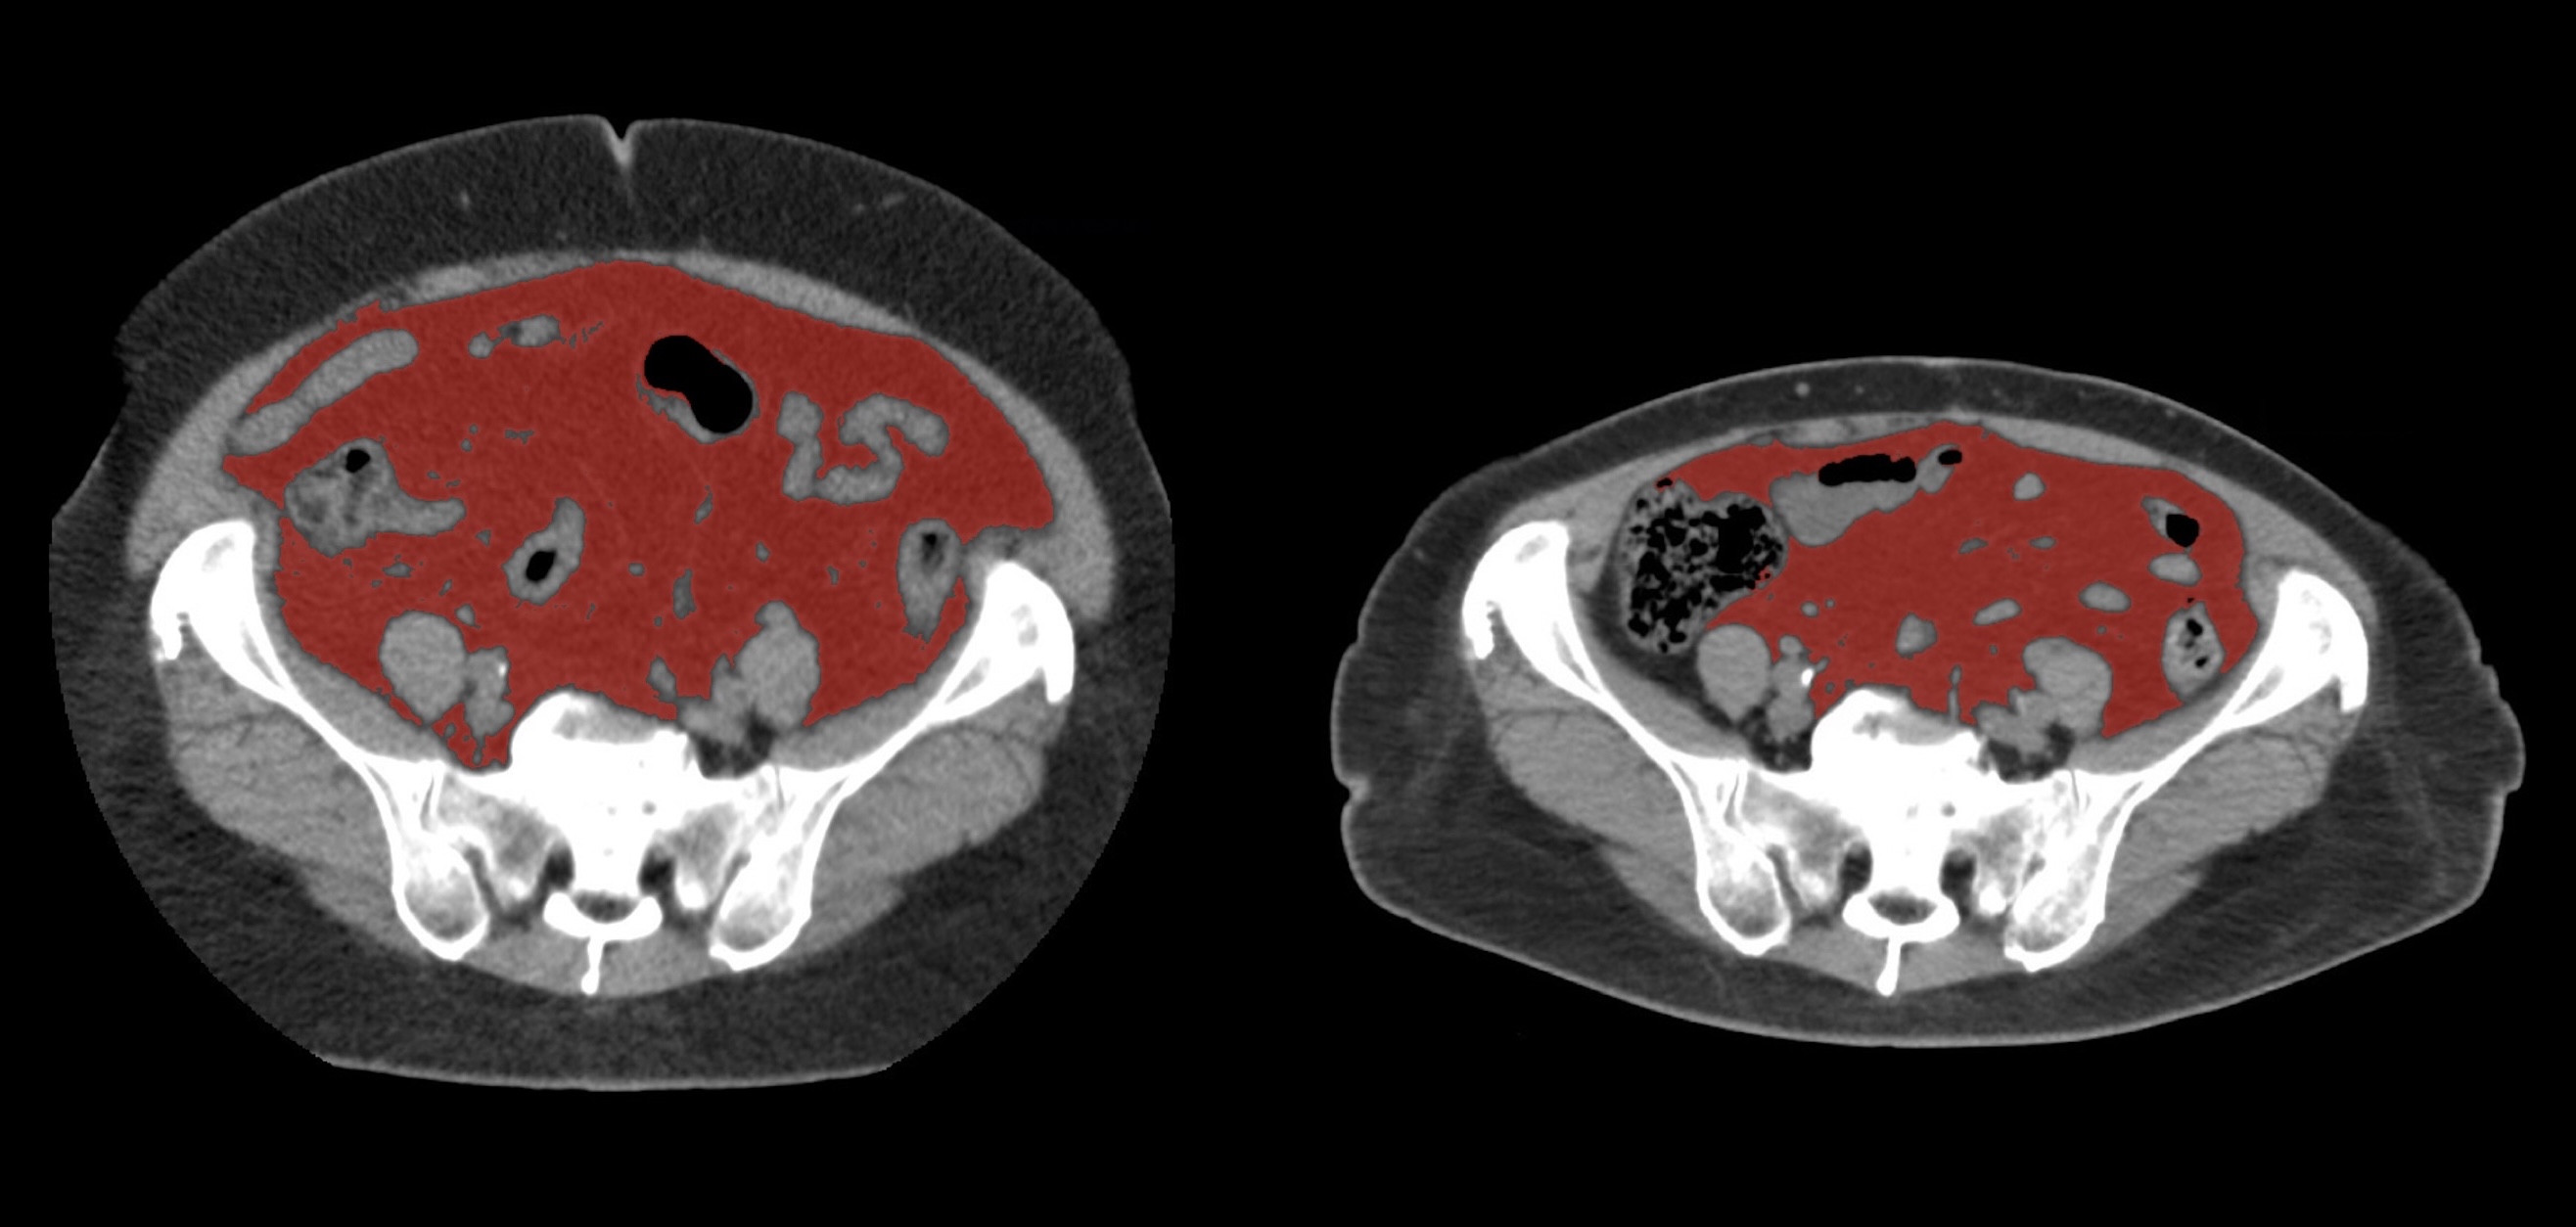

①

50代・女性(ご本人のご厚意で画像提供)

治療内容:チルゼパチド7.5mgの週1回自己注射による脂肪減少と脂肪肝改善

治療期間: 12ヶ月(52週)((用量は2.5mgから開始し最大で15mg。減量効果が得られる必要用量には個人差があります。))

費用:自由診療の場合は9900円(税込)×52(週)=514800円

想定されるリスク・副作用:下記に副作用を記載

※医療広告ガイドラインに準拠して表記

1:脂肪の減少

皮下脂肪の減少(赤色部分)